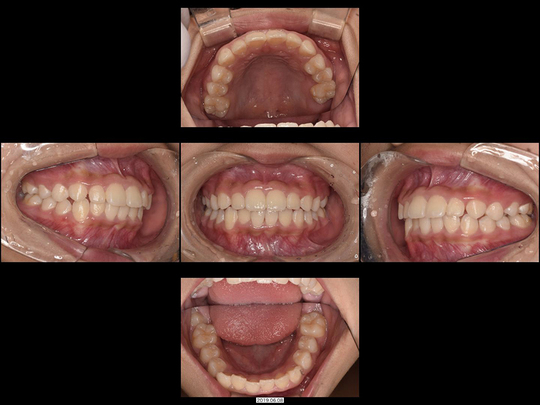

Mさん 開始時9歳 女性

矯正前

画像をクリックで拡大

矯正後

上下の前歯がガタガタで、中学生になってから抜歯するしかない。それまでは様子を見ましょうと言われたケースです。当院での治療スタート時が1期治療後半の時期であり、一般的には対応は困難かと思われる状態でした。

ところが精査の上、あごの骨年齢的にまだ拡大可能であることが判明。ワイヤー矯正なし、通常通りの固定式拡大装置の非抜歯矯正で対応しました。

治療の期間・回数

36か月、36回

​費用

576,400円